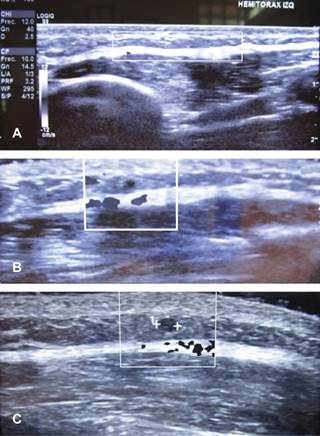

Figura 2: Estudio de ultrasonografía. A) Corte sagital. B) Doppler (color negativo). C) Corte transversal. Se muestra trayecto vascular subcutáneo inflamatorio de 7 cm de longitud y 4 mm de diámetro, no se modifica con maniobras de compresión y corresponde a tromboflebitis de vena superficial de hemitórax izquierdo. (Enfermedad de Mondor).

La ecografía es la elección para corroborar diagnóstico, se identifica el trayecto del vaso superficial afectado que muestra una estructura tubular alargada, anecoica y sin flujo en el Doppler.5